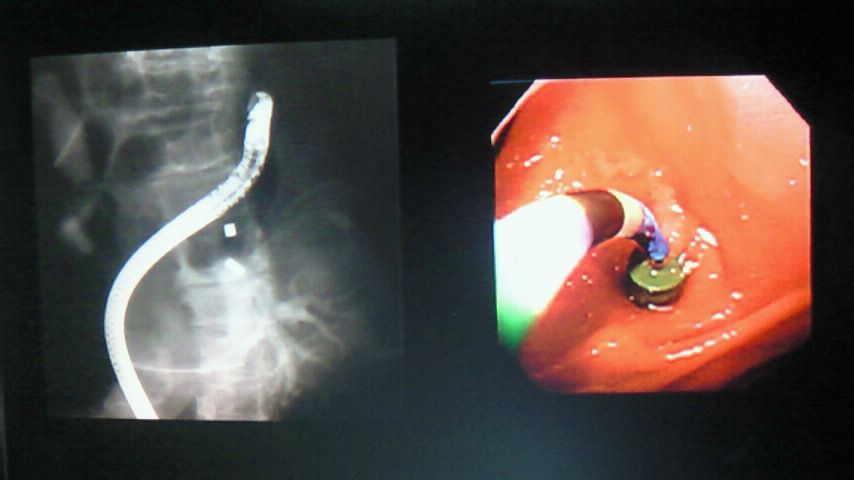

以下の画像は人間の胃の中を撮影したもので、ネオジム磁石が腸管をつないでいます。

腸閉塞や総胆管閉塞などの場合にネオジム磁石を腸管の内腔へ留置し、吸着させておけば自然にバイパスが出来て回復に至るという画期的な手法です。

手術ではないので全身麻酔の必要も無く、ガン末期の腹水で手術が出来ない人でも、この手法なら可能となります。

聖マリアンヌ医科大学、放射線科の山内栄五郎先先がご考案され、15年程前から色々な磁石で試行錯誤され、1998年に世界で初めて施術に成功されました。